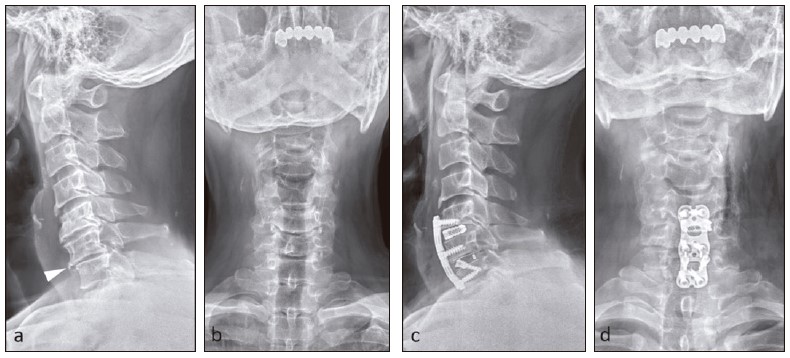

Figure 18

Degenerative spondylolisthesis in a 61-year-old man who presented with neck pain. Initial (a) lateral and (b) AP cervical spine radiographs show mild loss of cervical lordosis, moderate C5/6 and C6/7 anterior and posterior osteophytes, mild C6/7 anterolisthesis (arrowhead) with C5/6 and C6/7 intervertebral disc space narrowing, worse at C6/7 level. There is C7/T1 facet degeneration. Follow-up (c) lateral and (d) AP radiographs following anterior cervical discectomy and fusion show C5-7 plate and screws with C5/6 and C6/7 disc implants. Alignment is restored.